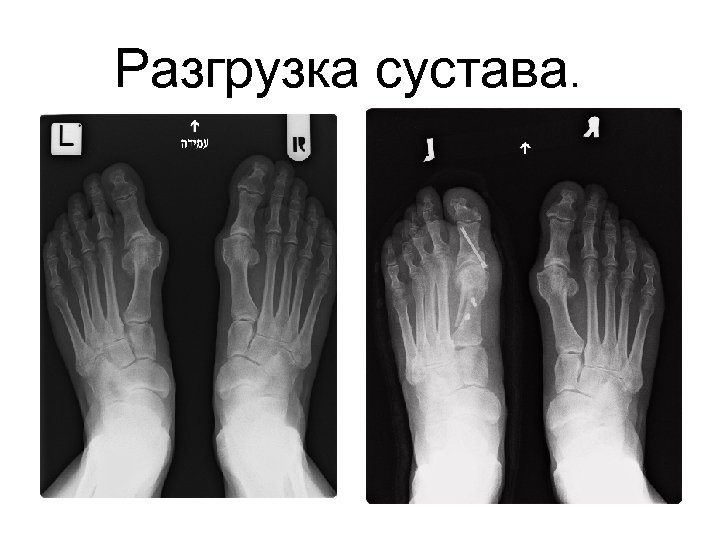

Ригидусная патология большого пальца • Артродез ( используя новейшие техники фиксации) • Разгрузка сустава. Ригидусная патология большого пальца • Артродез ( используя новейшие техники фиксации) • Разгрузка сустава. • Ендопротезирование 1 метатарзо фалангеального сустава ( Total Toe Replacement)

Разгрузка сустава. Разгрузка сустава.